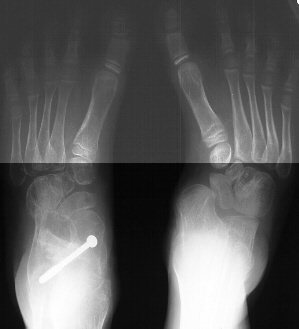

Due to persistent foot pain and excessive callus formation over the

medial arch the patient was taken to the OR and underwent surgical treatment

of the left foot. The procedure consisted of :

- subtalar arthrodesis with autograft bone graft and screw fixation

- closing wedge calcaneocuboid arthrodesis with open pinning

- reduction and open pinning of the talonavicular joint

- midfoot soft tissue release of the talonavicular, calcaneocuboid and

subtalar joints

Post operatively, the patient was placed in a long leg cast. Preliminary

results show satisfactory reduction of the talonavicular joint, correction

of hindfoot valgus, dorsiflexion of the talus on the calcaneus, and correction

of forefoot adduction immediately post op.